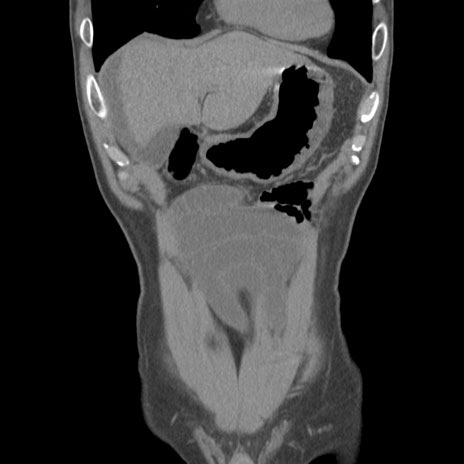

症例56 CT(冠状断像)

脂肪ウインドウ